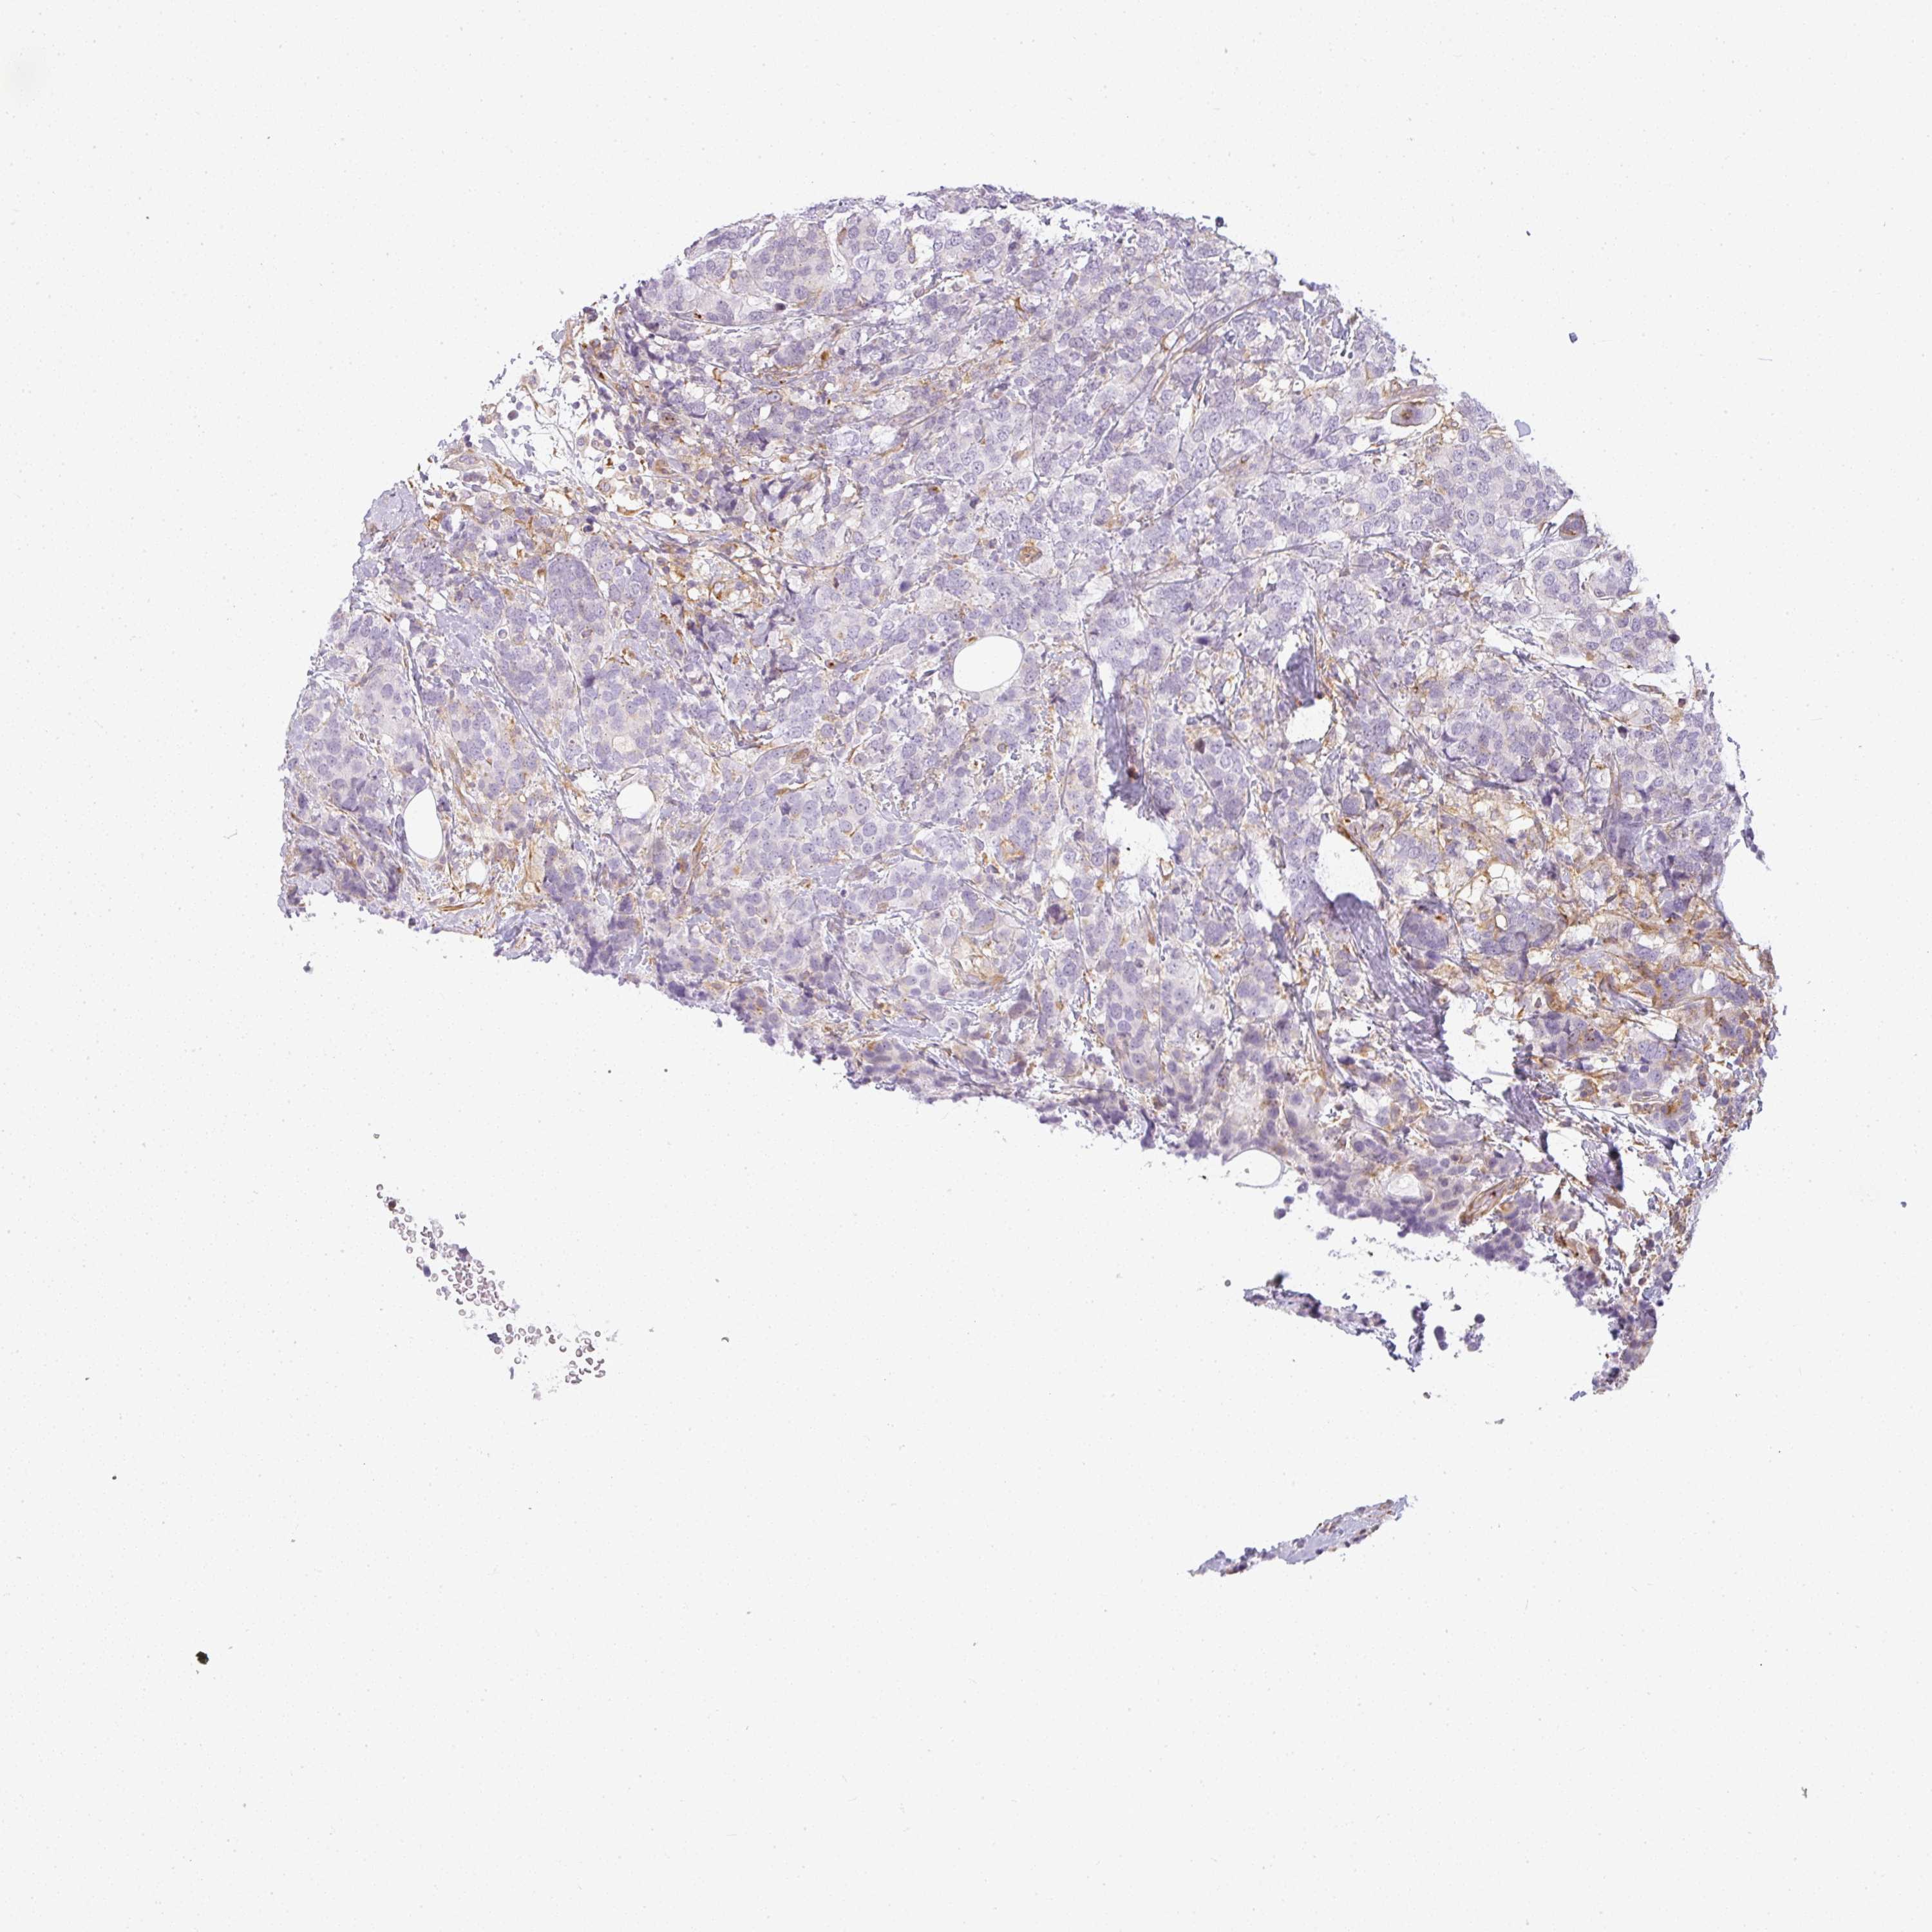

CANCER BREAST CANCER Show tissue menu

BRCA TCGA BRCA VALIDATION PROTEIN EXPRESSION

Breast cancer

Human cancer